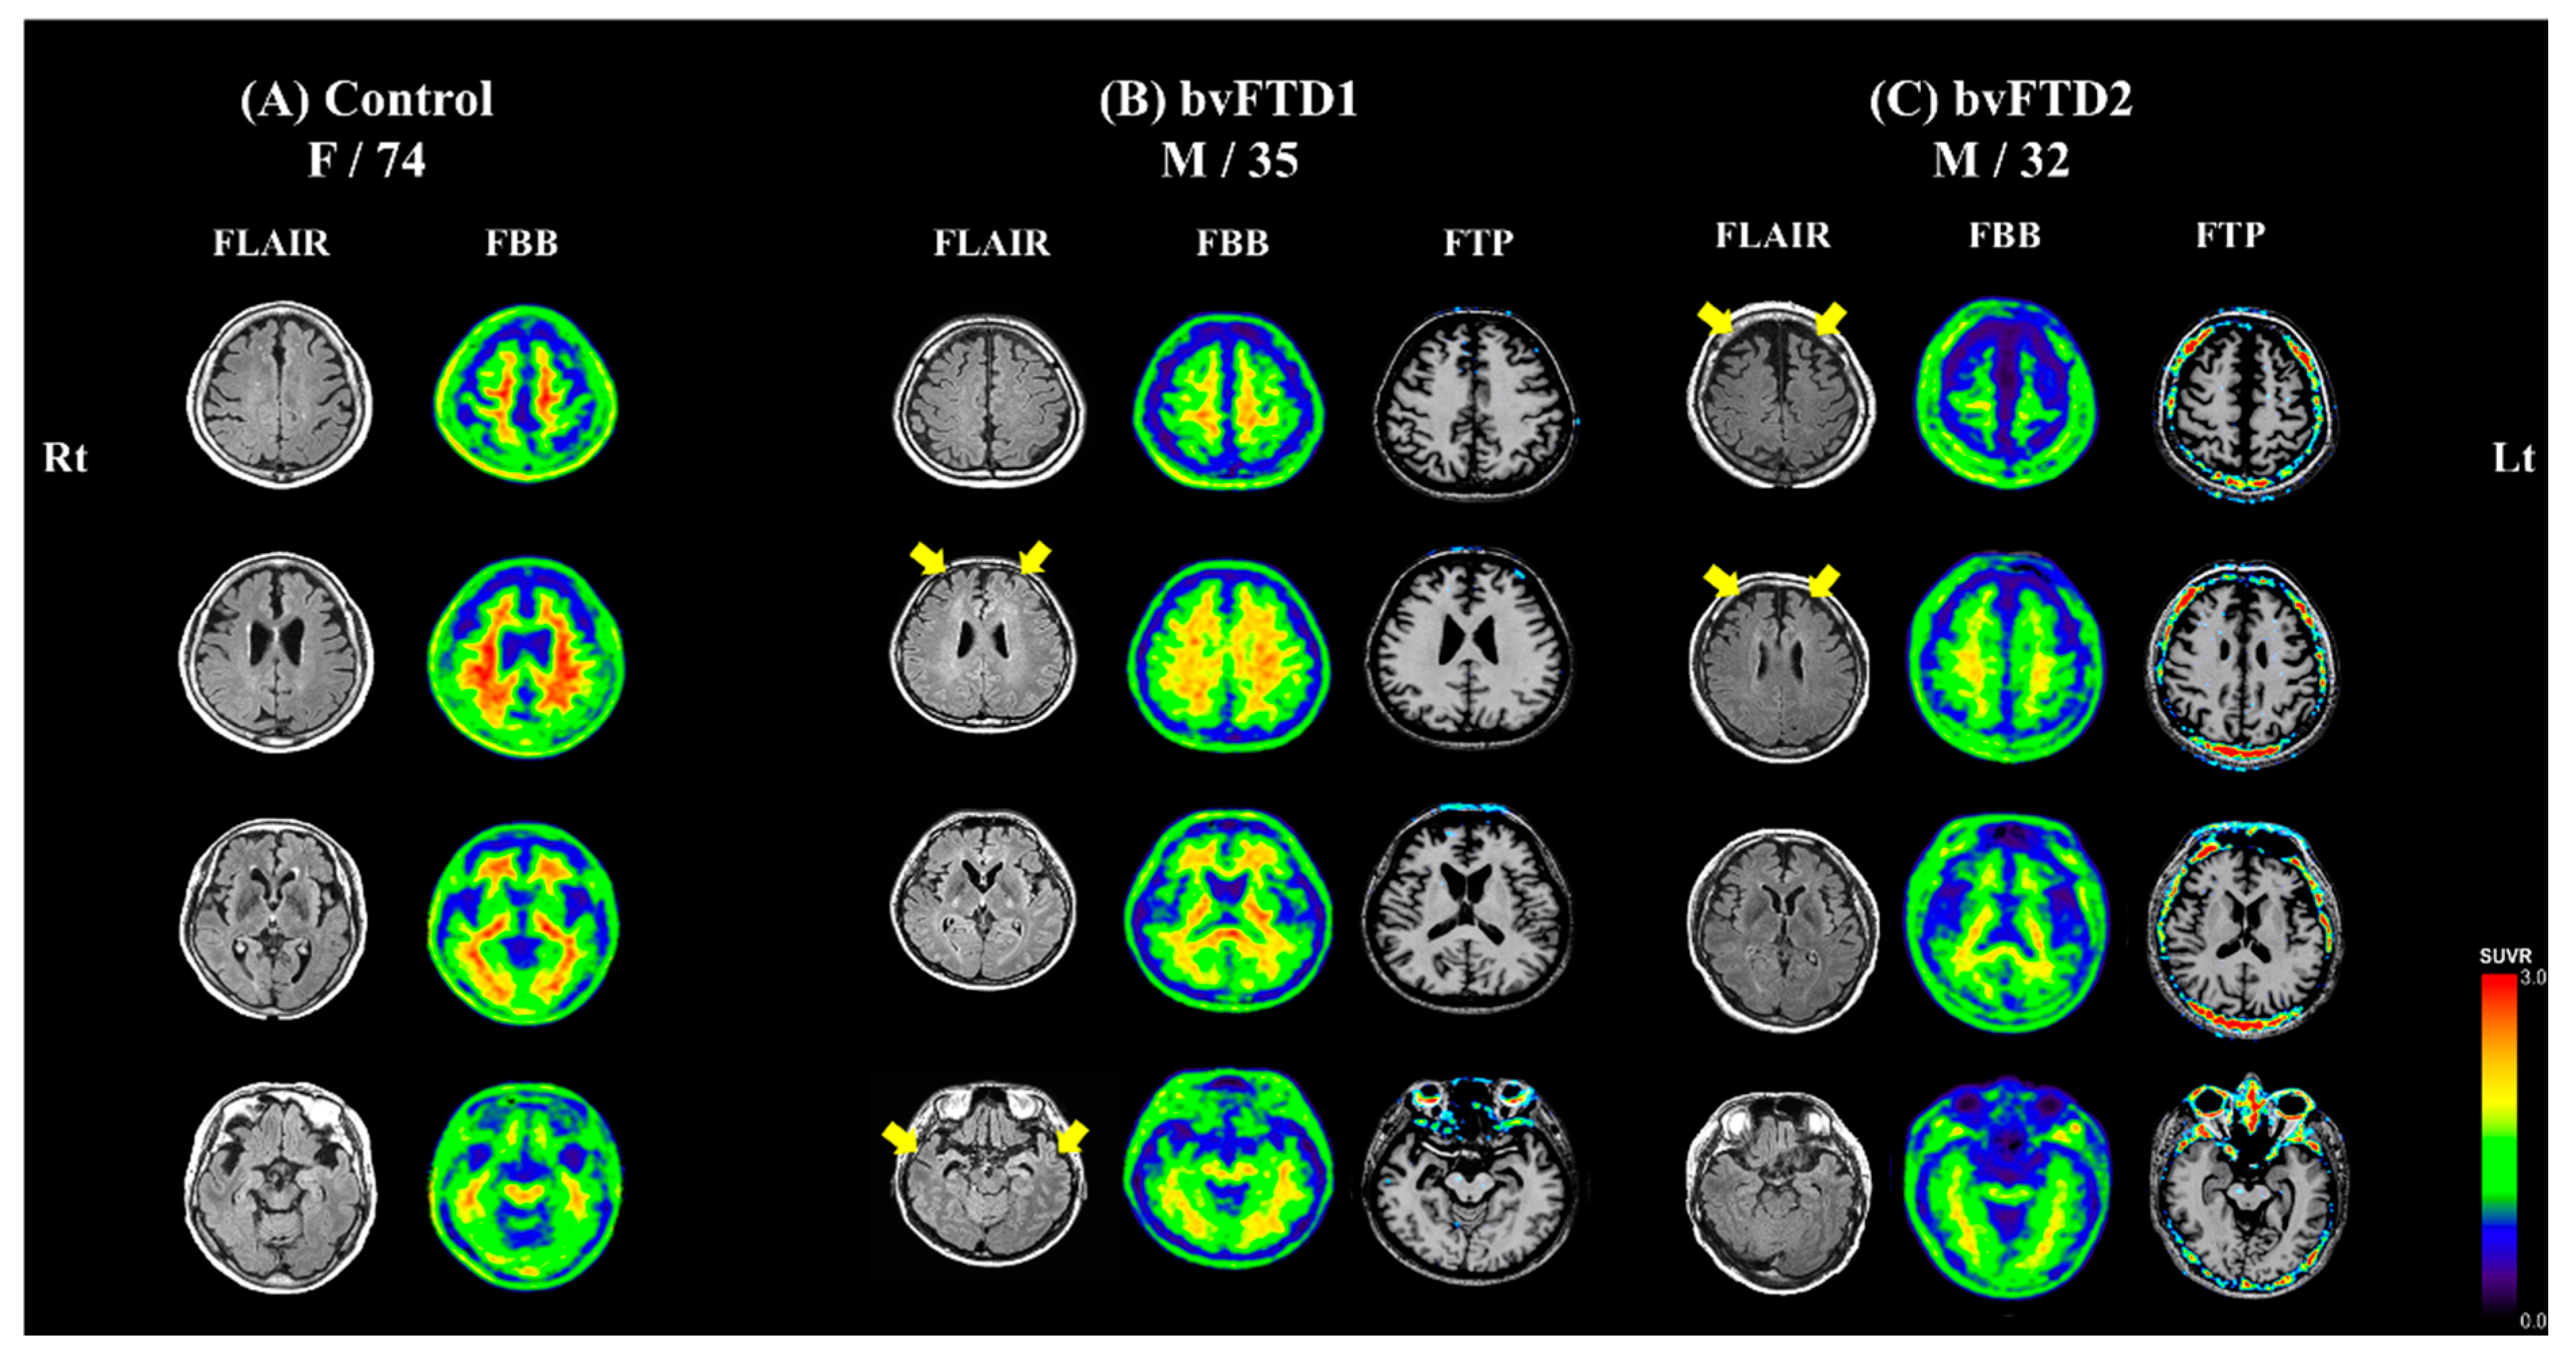

2.1. Case Description